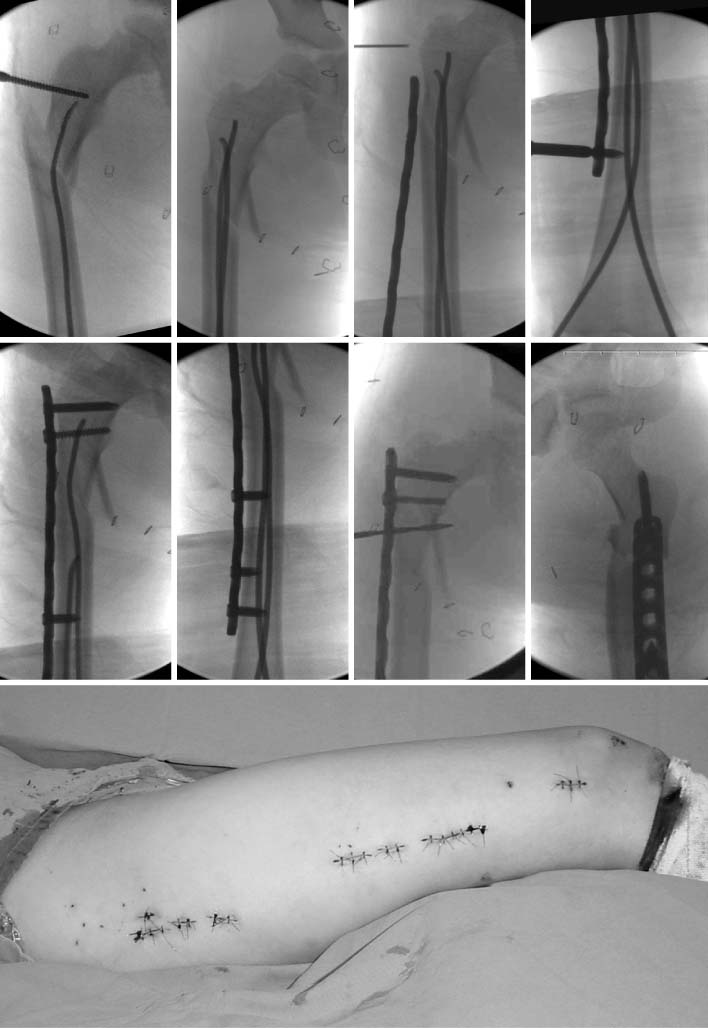

Fig. 5

These are the sequence of operatingprocedure in the suggested patient of Fig. 1. After the temporary reduction of femoral fracture with flexible nails, the plate was introduced through the submuscular tunnel. Then, the locking screws were fixed at the proximal and distal sides of the plate. The fracture site was not open to preserve the biology. The flexible nail makes an easier reduction of fracture, which facilitates the minimally invasive plate osteosynthesis (MIPO) procedure.